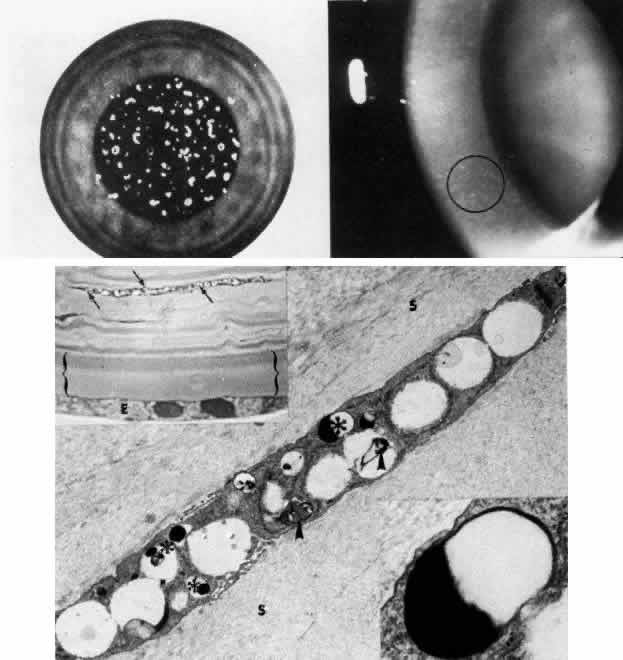

Lattice Dystrophy

Lattice dystrophy is an autosomal dominant condition characterized by pathognomonic, branching “pipestem” lattice figures within the stroma (Figs. 5 AND 10; Color Plate 1G). Symptoms usually begin in the first decade of life and include decreased vision as well as recurrent erosions because of subepithelial and stromal accumulations of amyloid material. In time, the condition progresses to involve marked opacification of the axial stroma, as well as in the superficial layers, leaving the limbus relatively free. At this stage, since the cornea also shows a superficial haze, it becomes difficult to visualize typical lattice lesions, and hence examination of younger affected family members is useful. Amyloid accumulation under the epithelium gives rise to poor epithelial-stromal adhesion with consequent recurrent erosion syndrome.49 The dystrophy advances inexorably, and by age 40 or earlier these problems become markedly aggravated, causing considerable discomfort and visual incapacity.

Fig. 10. Lattice corneal dystrophy. Top. Slit lamp photograph demonstrates pathognomonic branching lattice figures throughout the stroma. Middle left. Phase-contrast photomicrograph shows subepithelial accumulations of fibrillar amyloid deposits (*) causing distortion of epithelial contour. B, Bowman's layer (paraphenylenediamine, × 800). Middle right. Transmission electron micrograph of basement membrane complexes reveals basement membrane irregularity and discontinuity resulting from underlying amyloid fibrils (× 21,000). Bottom left. Transmission electron micrograph of stroma shows normal collagen fibrils and keratocytes with electron-dense material abnormally dispersed extracellularly (× 16,000). Bottom right. High-magnification transmission electron micrograph resolves lattice material as masses of fine, 8- to 10-nm diameter amyloid fibrils (circled below) in comparison with larger-size stromal collagen fibrils (above) (× 75,000). (Slit lamp photographs courtesy of WJ Stark, MD)

Many published reports have documented the nature of the corneal deposits in lattice dystrophy. In 1961, Jones and Zimmerman99 and others suggested that the disorder was due to amyloid degeneration of the stromal collagen fibers. In 1967, Klintworth111 confirmed that the disorder was a familial form of amyloidosis limited to the cornea and showed that the fibrillar material stained with Congo red and exhibited the birefringence and dichroism typical of amyloid. On transmission electron microscopy, the fine, electron-dense fibrils of 8 to 10 nm diameter are similar to those of known amyloid fibrils. Using fluorescence microscopy, staining with thioflavin-T is helpful in further characterizing the amyloid material, as are immunofluorescent studies using antihuman amyloid anti-sera.112 Evaluation of corneas with typical lattice dystrophy has demonstrated the presence of the amyloid P (AP) component, but staining for amyloid A (AA) protein has remained controversial.113–117 The corneal endothelium and Descemet's membrane are not involved. Moreover, amyloid deposits have not been found in other excised tissues from patients with typical lattice dystrophy.111

The specific etiology of the amyloid deposits is, as yet, unclear. They may be secondary to collagen degeneration, perhaps from lysosomal enzymes elaborated by abnormal keratocytes. An alternative theory holds that abnormal keratocytes actually produce the abnormal amyloid substance, although this process is not ultrastructurally evident.

Treatment of this disorder is symptomatic, depending on visual acuity and patient discomfort. Penetrating keratoplasty in this condition carries an excellent prognosis, although recurrence of the dystrophy in the graft may take place.118–121